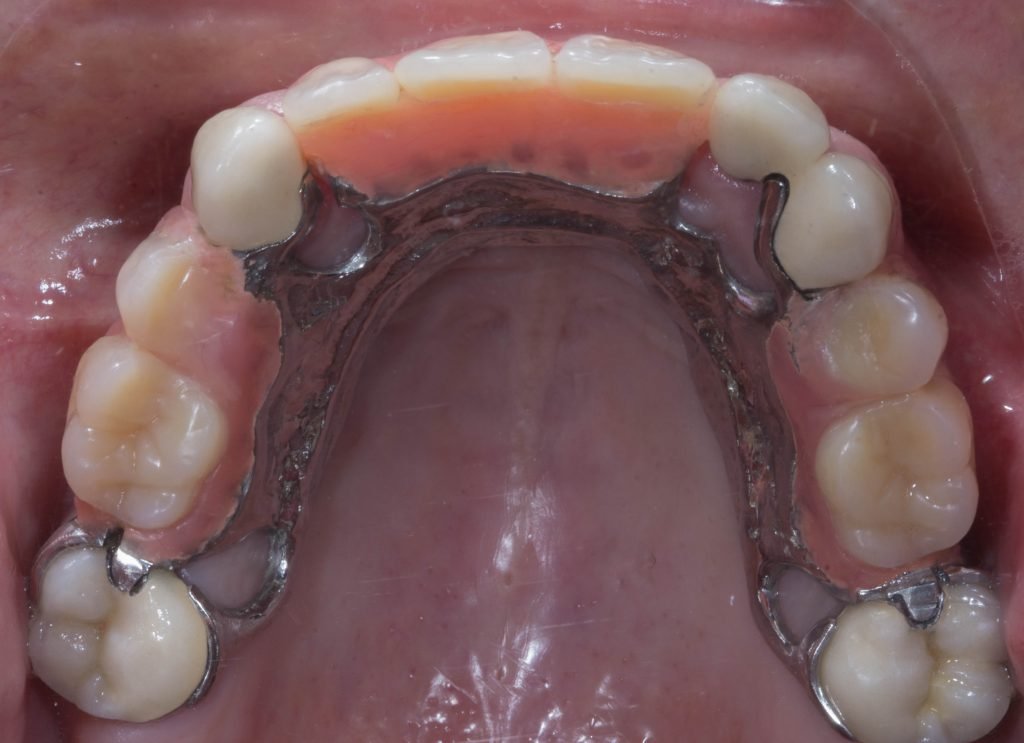

Punto Bajío Casos Clínicos Prótesis Fija sobre Implante unitario Inicio Provisional Final Prótesis Parcial Fija sobre 2 Implantes 2 Implantes Final Prótesis Bucal Removible Inicial Inicial Superior Inicial Inferior Rayos X Inicial Rayos X Inicial Frontal Final Final Superior Final Inferior Prótesis Parcial Fija/ Coronas de Circonio Sonrisa Inicial Foto Inicial Foto Inicial Inferior Foto Final Inferior Foto Final Sonrisa Final Prótesis Total Protesis Inmediatas 1 Protesis Inmediatas 2 Prótesis Removible/ Coronas Metal-Ceramica Carillas Incrustaciones Endodoncia